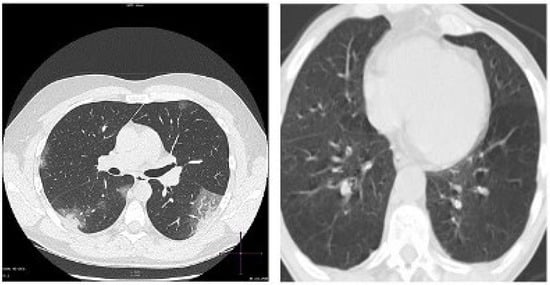

5.1.2. CT Scan Imaging

5.3.2. AI-Powered Detection of COVID-19 from CT Scans